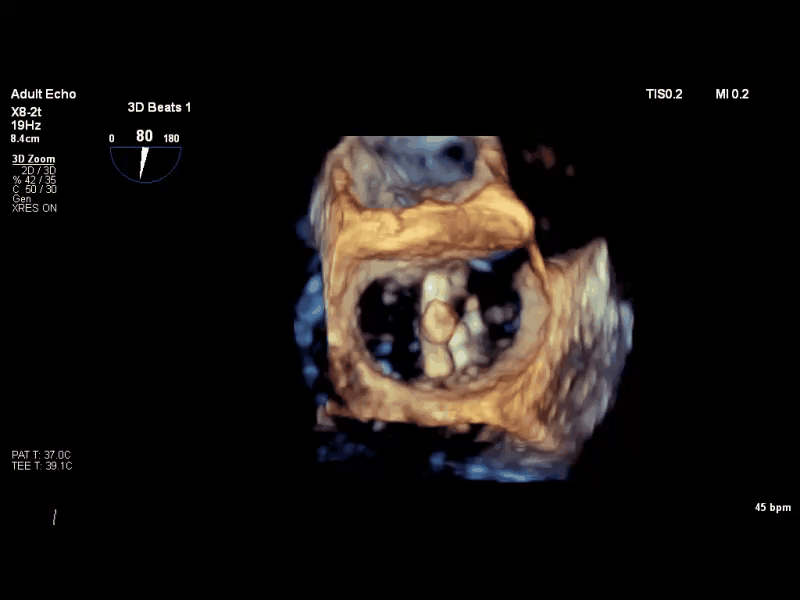

术前TEE 3D

经食道超声心动图(TEE)提示:二尖瓣病变Carpentier II型,DMR,二尖瓣2区反流及P2腱索断裂并瓣叶脱垂,Gap 6 mm,Width 15 mm, 瓣口面积6.7 cm²,2区前叶长20 mm,后叶长19 mm。MR4+,反流束来自于2区,偏心性反流束,指向前叶;VC 11 mm。房间隔穿刺空间约4.5 cm。